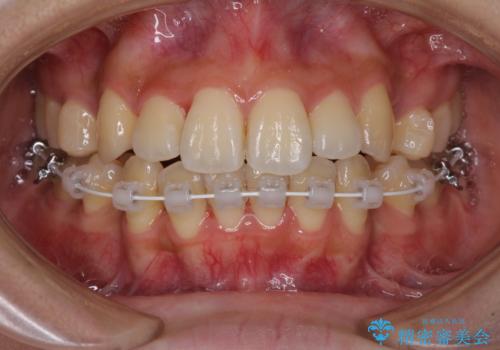

- ハーフリンガル

- 2年6ヶ月

目立たない装置を希望されたので、上顎が裏側装置のハーフリンガルを選択し、上下左右の小臼歯(計4歯)を抜歯して矯正治療を行うこととしました。